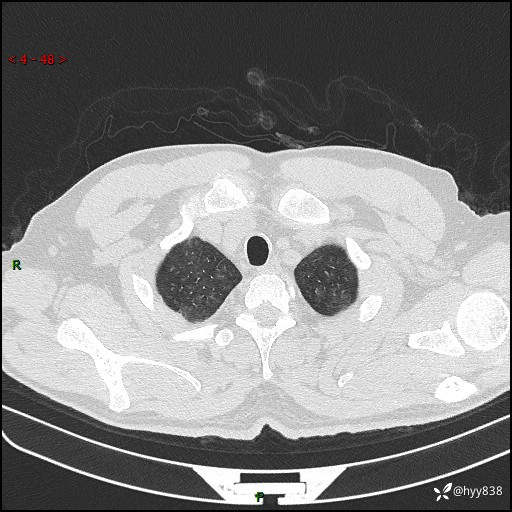

昨天肺结节门诊,“对门”呼吸科申请会诊病例,弥漫性肺部病变---结果公布~

患者年龄:51岁

主诉:发热、咳嗽、咳痰1周

简要病史:患者1周前无明显诱因出现咽喉部疼痛,随后出现咳嗽咳痰,起初干咳为主,后出现咳少许绿色痰,当时有发热,体温为39℃,无畏寒寒战,无胸闷胸痛,无活动后气短,无咯血,无鼻塞流涕,无全身酸痛,患者于诊所输液治疗后体温正常,但仍有咳嗽。患者3天前当地县人民医院就诊,患者仍有咳嗽,咳嗽较为频繁,咳嗽后出现头痛,伴有少许咳痰,随后出现活动后气短,1天前患者再次出现发热,体温最高为40℃,伴有畏寒寒战,伴有乏力、纳差,伴有胸闷不适,无咯血,无全身皮疹,无血尿、尿频尿急尿痛,无腹泻,诊断为“重症肺炎 感染性休克 肾功能异常 痛风”;予以抗感染(亚胺培南),抗病毒(奥司他韦)等对症治疗。患者复查胸部CT提示双肺病灶较前有所增多,建议上级医院就诊,门诊以“肺部感染”收入我科。 起病以来,患者食欲欠佳,大小便正常,睡眠、精神欠佳,体力下降、体重无明显变化。

辅助检查:CT

临床诊断:肺部感染

胸部HRCT